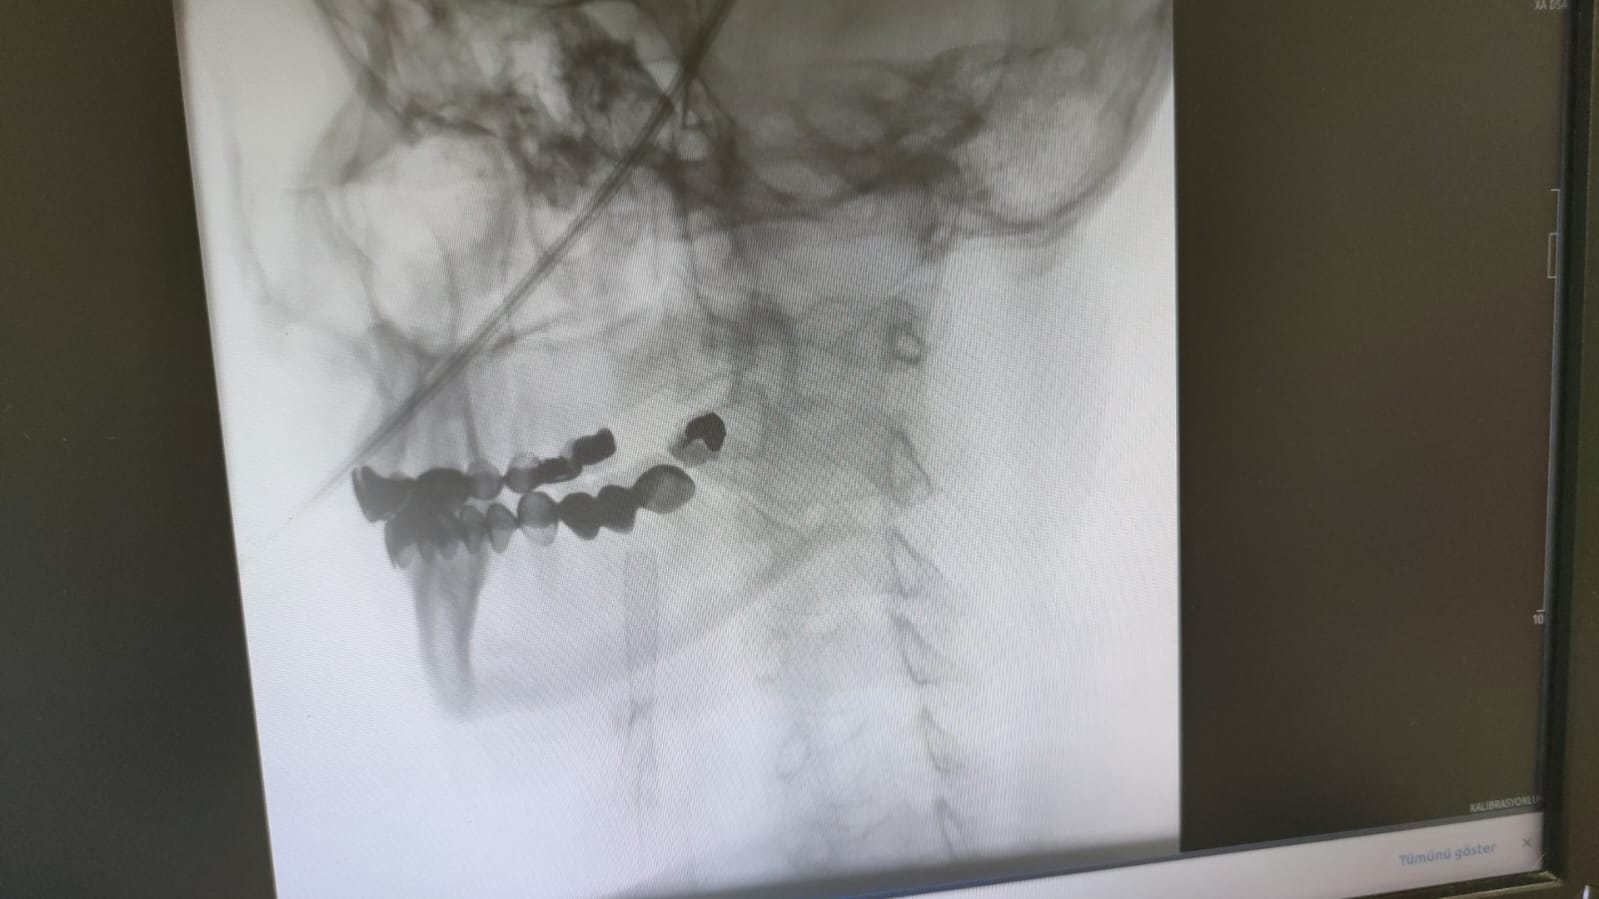

Stentleme işlemi, femoral arterden (kasık atardamarı) girilerek ince kateterler ve özel stentler aracılığıyla daralmış damarları açmayı kapsıyor. Böylece beyne giden kan akışı güvence altına alınarak felç riski büyük ölçüde azaltılıyor. İşlemin ameliyatsız olması, hastaların kısa sürede normal yaşamlarına dönmesini sağlıyor. Doç. Dr. Gündüz, “İşlem sorunsuz geçerse hasta ertesi gün taburcu olabiliyor. Hem konforlu hem hızlı bir iyileşme süreci sağlanıyor” dedi.

Uzmanlar, bu işlemin yalnızca donanımlı merkezlerde ve deneyimli hekimler tarafından yapılabileceğini belirtiyor. Doç. Dr. Sezer Eryıldız, “Girişimsel anjiyografi cihazı olan ve yeterli vaka deneyimine sahip merkezlerde güvenle uygulanabilir” diye konuştu.